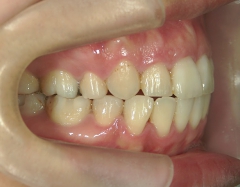

矯正歯科 治療前矯正歯科 治療前

矯正歯科 治療前 上下左右4番 計4本を抜歯して叢生を改善しました。

no.31_1962_治療前_右.JPGno.31_1962_治療前_正面.JPGno.31_1962_治療前_左.JPG